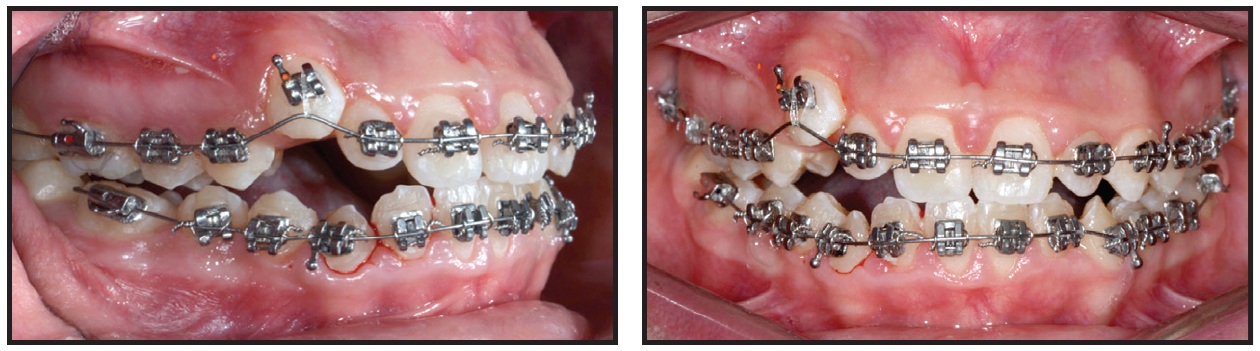

Two months later, the brackets on the upper right central incisor and lower right first premolar were repositioned for finishing and detailing, and Class III elastics were applied asymmetrically to center the upper and lower dental midlines (Fig. 10).

Fig. 10 Two months later, brackets repositioned on upper right central incisor and lower right first premolar for finishing and detailing.